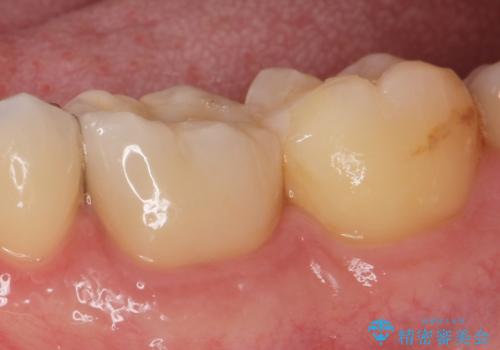

銀歯の下の虫歯|オールセラミッククラウン

担当医 河野豊嘉